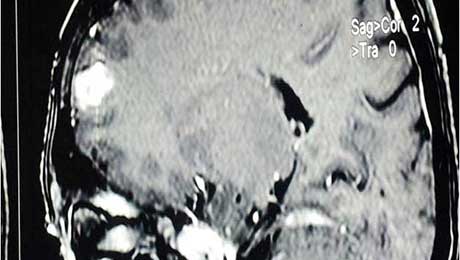

Dnet t2w